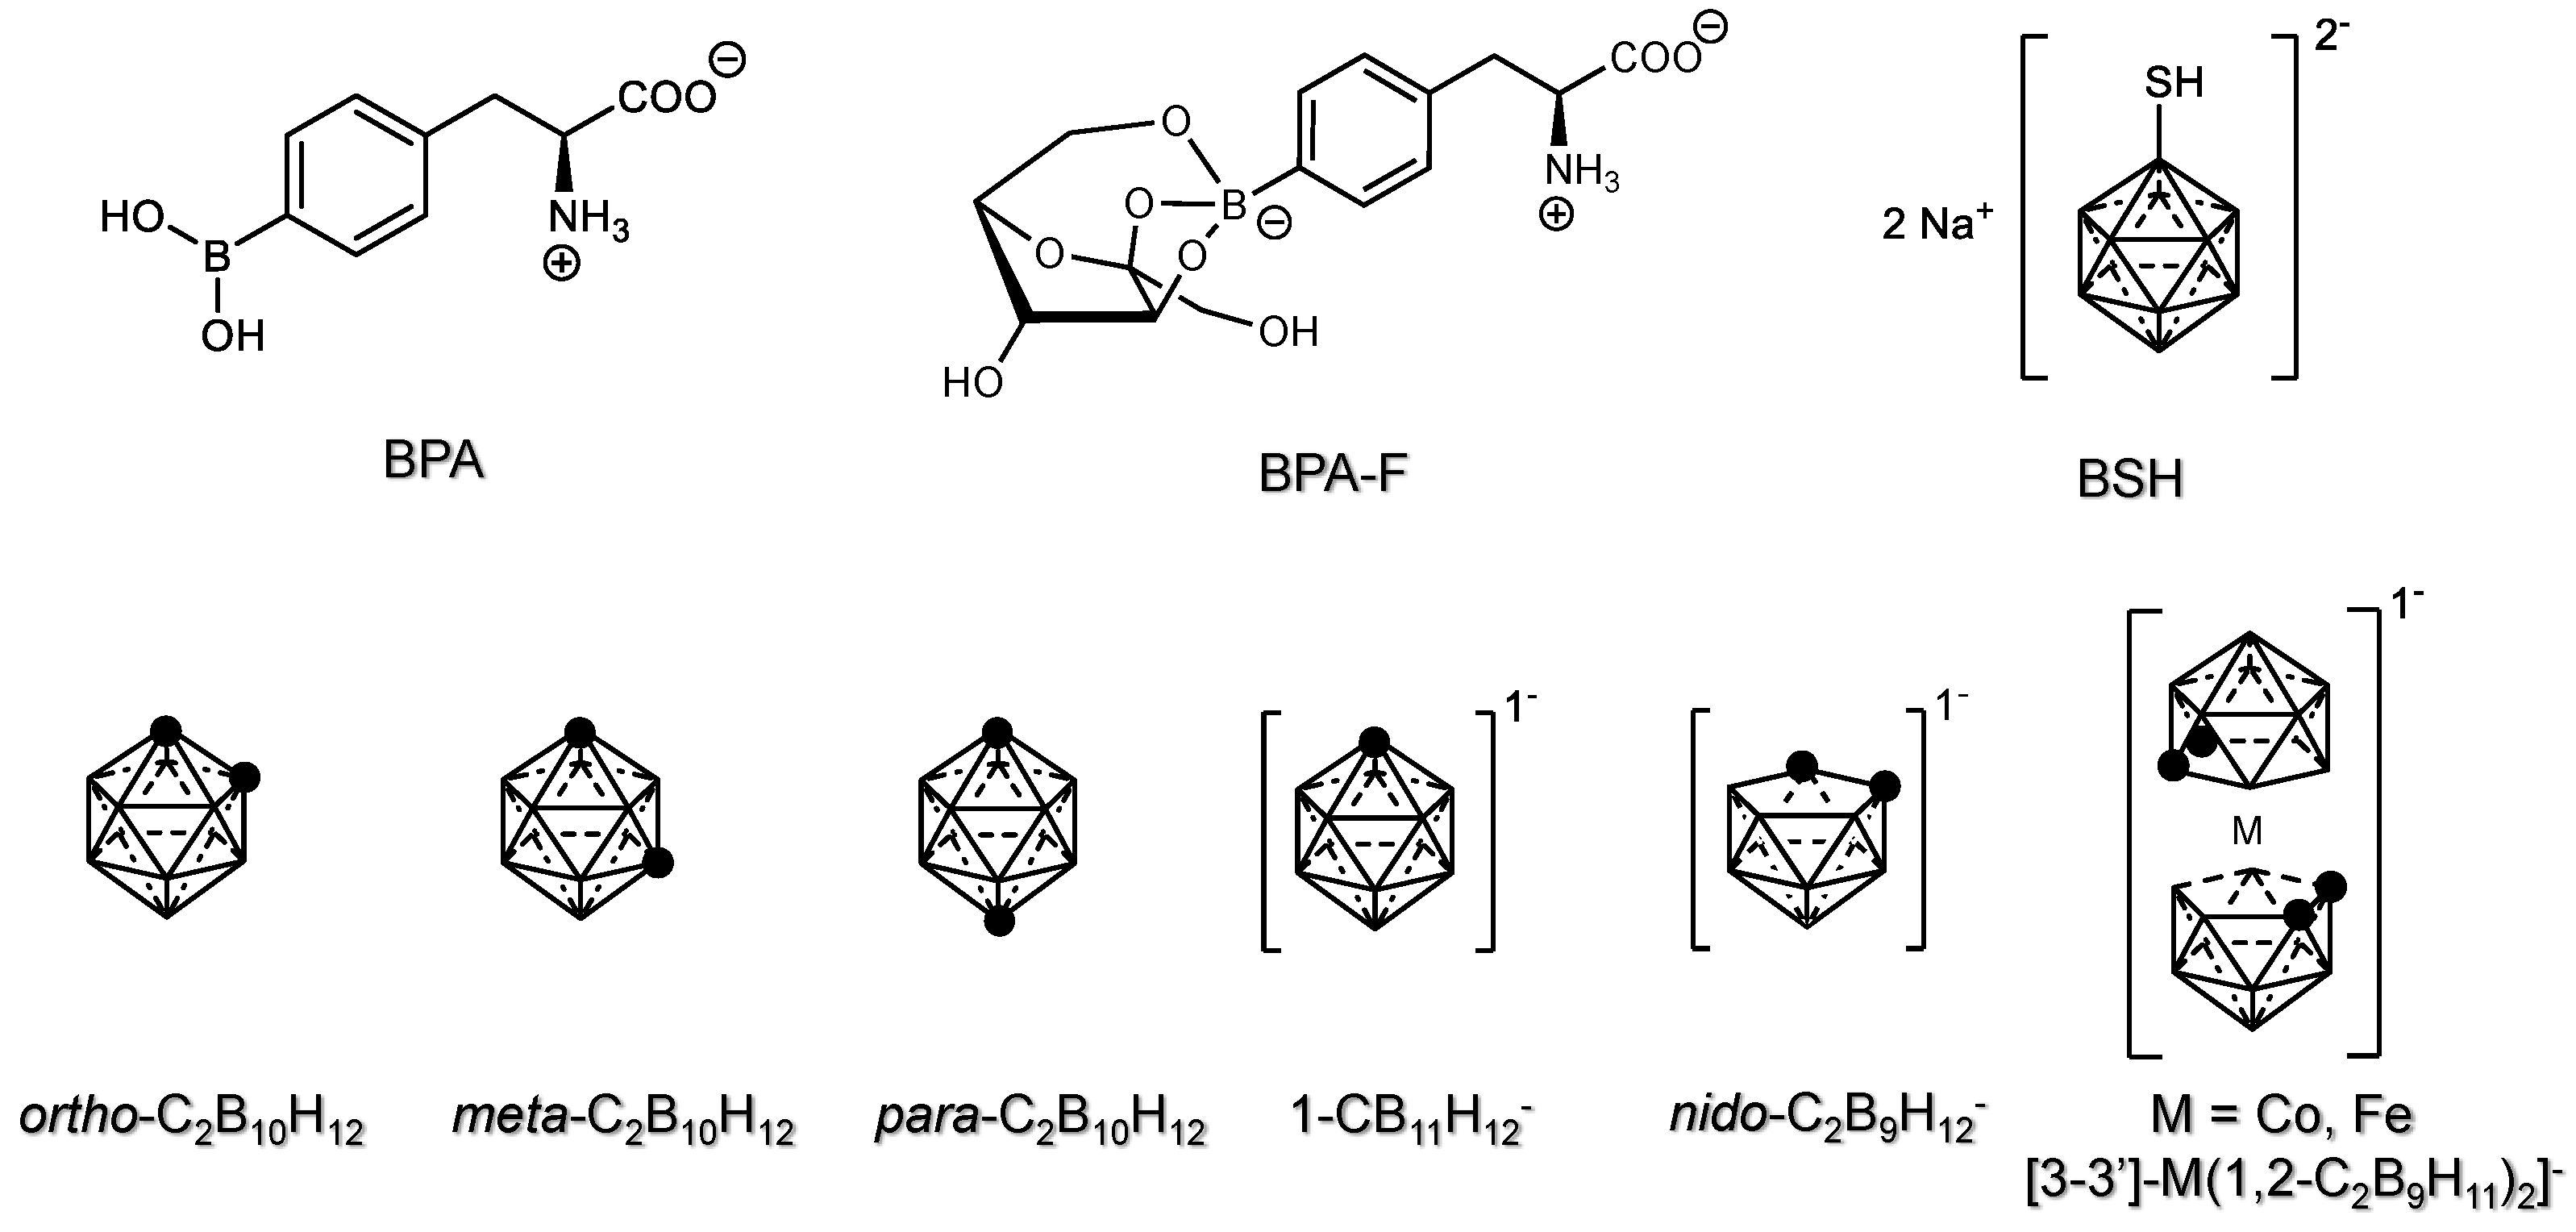

2. In Vivo Studies of Carboranes for BNCT

2.1. Chemical Derivatization of Carboranes for In Vivo Studies